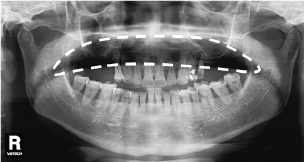

5. Несоответствие параметров экспозиции Kv, mA.

Рис. 6, Рис.7. Искажения из-за несоответствия параметров экспозиции Kv, mA.

Нужно сказать, что данная ошибка, к счастью, возникает не так часто. Выбор настроек экспозиции осуществляется в автоматическом режиме, благодаря информации о дате рождения пациента из его карточки. Однако, в случае, когда данный параметр остается не заполненным, параметры экспозиции могут быть выбраны неадекватно относительно пациента.

Что делать:

- На подготовительном этапе исследования при создании карточки пациента укажите дату рождения пациента.

- Если настройки экспозиции избыточны (рис А) – уменьшите Kv, mA.

- Если настройки экспозиции недостаточны – увеличьте Kv, mA